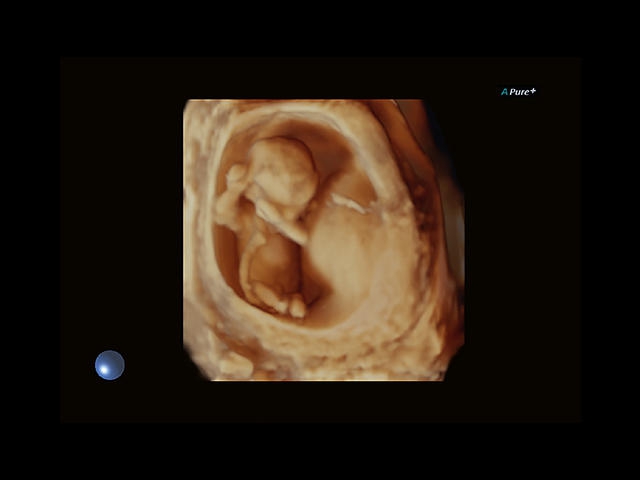

Обновленная версия легендарного УЗ-сканера. Стационарный аппарат экспертного класса Aplio 500 Toshiba NEW, визуализирует анатомические структуры в высоком разрешении. Модель позволяет выявить микрокальцификаты, новообразования, нарушения в работе сердца, сосудов и мышц. Присутствует функция виртуальной эндоскопии, 4D-сканирования, эластометрии тканей, УЗИ с контрастированием. За повышение качества изображения отвечают технологии ApliPure и Superb Microvascular Imaging. Первая задействует возможности пространственного и частотного кодирования, формирует цельный визуальный ряд с сохранением клинических маркеров. Вторая улучшает отображение микрососудистого русла, используя доплеровский эффект. Модель оснащена 21-дюймовым монитором, имеет 4 активных порта. Возможно подключение педиатрических, интраоперационных, лапароскопических и чреспищеводных датчиков.